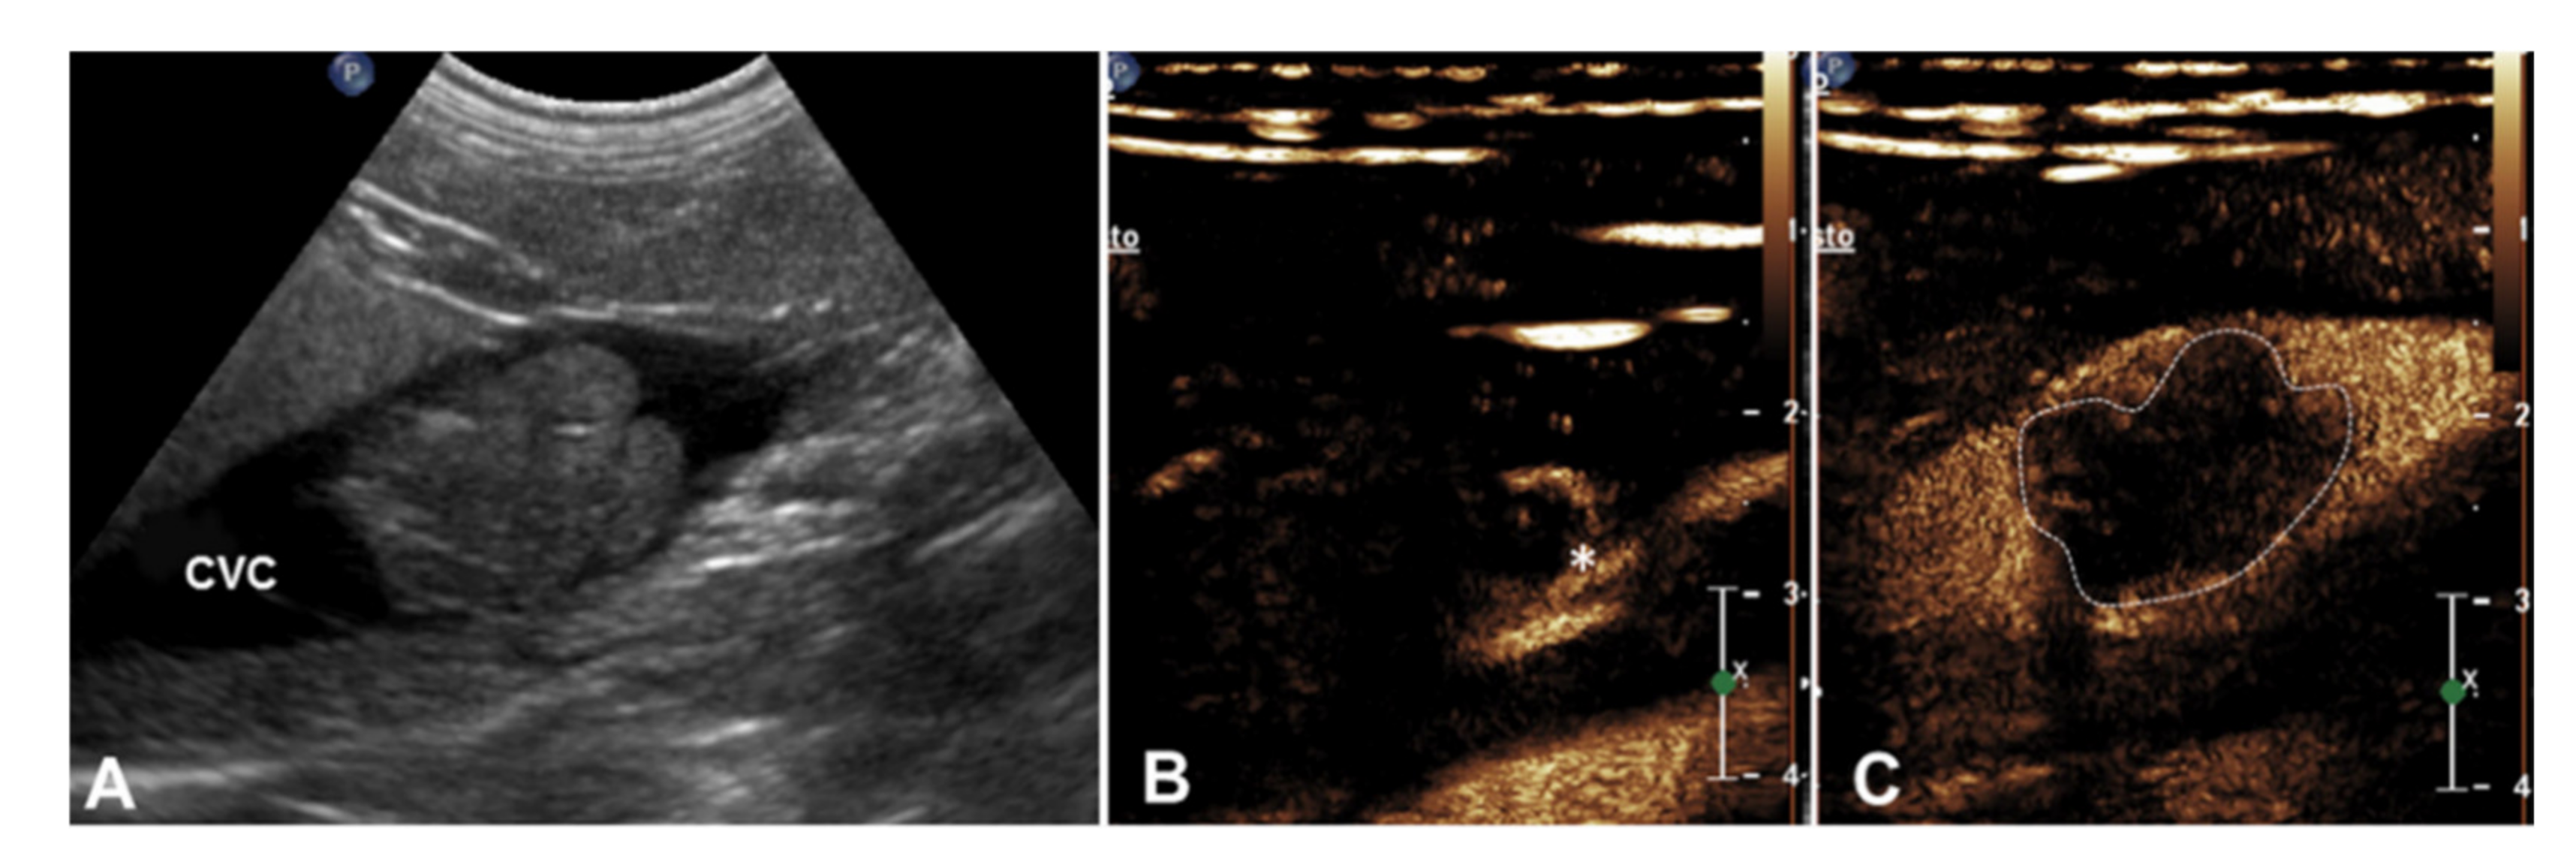

| 5 | Right adrenal pheochromocytoma | Caudal vena cava | 1 Heterogeneous mass on the right adrenal gland (5 cm) | Intravascular homogeneous mass with vessel distension | Residual flow within the lumen of the vessel | Present | Heterogeneous | Regular and well-defined | Earlier | Simultaneous |